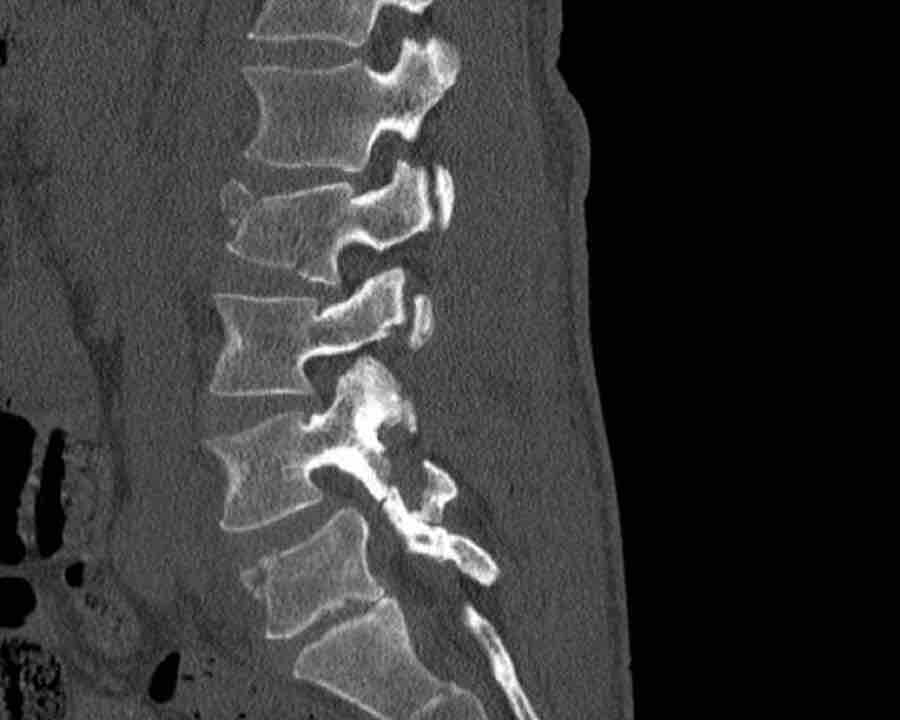

A2 Split fracture

A2 is a fracture of both endplates without involvement of the posterior wall of the vertebral body.

What is the highest AO-type of injury?

Findings:

- No C or B injury

- Fracture of the vertebral body with involvement of both endplates (1+1 points), no posterior wall involvement

Conclusion

injury type A2